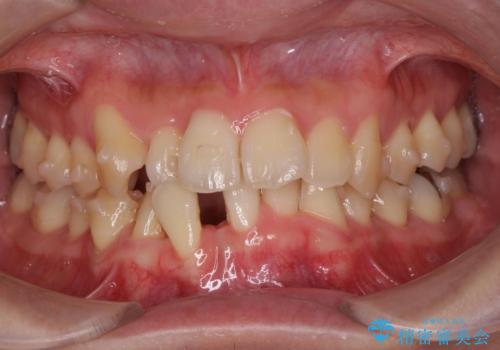

ねじれ・がたつきのある前歯を改善

- がたつき・すれ違い、ねじれのある前歯の見た目、噛み合わせの改善を希望され来院されました。

4本の小臼歯抜歯を避け、下顎前歯の1本抜歯の極力少ない抜歯本数で審美的な歯並びを得る治療計画としました。

すれ違いを治すのが得意な前歯部の部分ワイヤーを用いることで、治療期間を短縮することができました。

見た目の改善だけでなく、噛みやすくなったことにも満足いただくことができました。